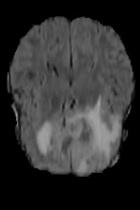

Current unsupervised anomaly localization approaches rely on generative models to learn the distribution of normal images, which is later used to identify potential anomalous regions derived from errors on the reconstructed images. However, a main limitation of nearly all prior literature is the need of employing anomalous images to set a class-specific threshold to locate the anomalies. This limits their usability in realistic scenarios, where only normal data is typically accessible. Despite this major drawback, only a handful of works have addressed this limitation, by integrating supervision on attention maps during training. In this work, we propose a novel formulation that does not require accessing images with abnormalities to define the threshold. Furthermore, and in contrast to very recent work, the proposed constraint is formulated in a more principled manner, leveraging well-known knowledge in constrained optimization. In particular, the equality constraint on the attention maps in prior work is replaced by an inequality constraint, which allows more flexibility. In addition, to address the limitations of penalty-based functions we employ an extension of the popular log-barrier methods to handle the constraint. Comprehensive experiments on the popular BRATS'19 dataset demonstrate that the proposed approach substantially outperforms relevant literature, establishing new state-of-the-art results for unsupervised lesion segmentation.

翻译:目前未受监督的异常本地化方法依靠基因模型来了解正常图像的分布,这些模型后来被用于确定从重建图像错误中得出的潜在异常区域。然而,几乎所有先前文献的主要局限性是,需要使用异常图像来设定一个特定等级的阈值以定位异常。这限制了其在现实情景中的可用性,在现实情景中,只有通常能获取正常数据。尽管存在这一重大缺陷,但只有少数作品通过在培训中整合对关注地图的监督,解决了这一局限性。在这项工作中,我们提议了一种新颖的提法,不要求使用异常图像来界定阈值。此外,与最近的工作相反,拟议的限制是以更加有原则的方式拟订的,在限制优化时利用众所周知的知识。特别是,先前工作中对关注地图的平等性制约被一种不平等性制约所取代,这允许更大的灵活性。此外,为了解决基于惩罚的功能的局限性,我们采用了流行的日志障碍方法来应对这一制约。我们建议对流行的BRATS'19数据设置进行综合实验,这与最近的工作不同,因此,拟议的限制是以更加有原则的方式提出了限制,即拟议的方法大大地超越了相关的分段结果。